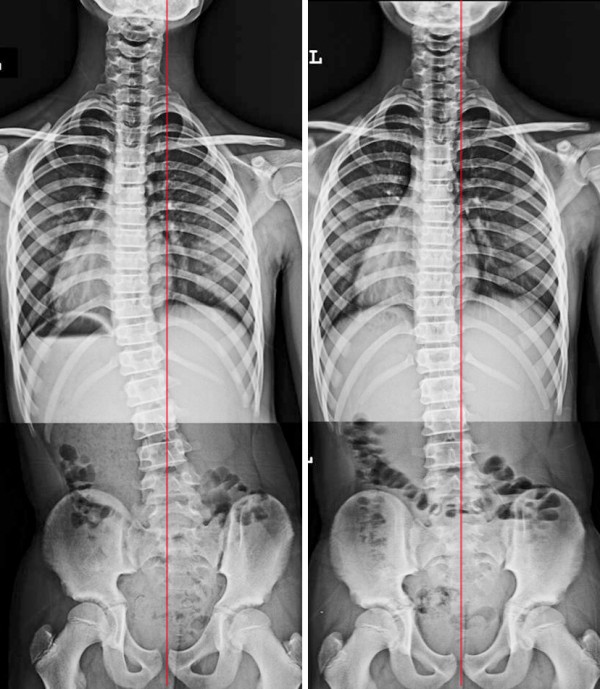

증상 : 등통증, 서거나 앉을 때 통증

치료기간(횟수) : 30회 치료, 4개월